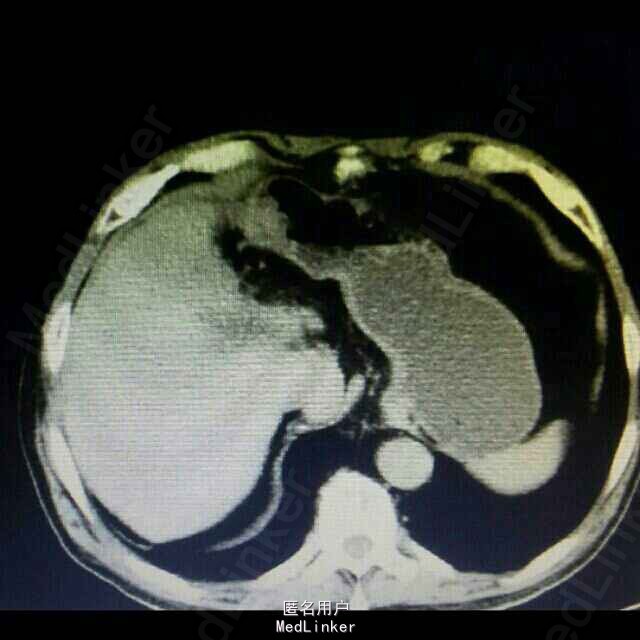

1、 主诉:上腹部疼痛4年余,加重2月。 2、 现病史:患者4年前无明显诱因出现上腹间歇性胀痛,可忍受,伴反酸、恶心、无呕吐,未予以治疗。患者2月前上腹部通天症状加重,伴肩部放射痛,伴反酸、恶心、无呕吐,未予以治疗。患者15天前因“感冒”就诊于当地医院行胸部CT示:肝左叶胆管结石并肝内胆管扩张、肝左叶萎缩。今患者为进一步治疗,前来我院就诊,门诊以“胆囊结石并急性胆囊炎”收入院,患者自发病以来精神状态可、食欲差,睡眠良好,大、小便正常,体重无明显变化。

3、 辅助检查:上腹部 CT平扫示:肝左叶胆管结石并肝内胆管扩张、肝左叶萎缩。胆囊结石,双肾囊肿。